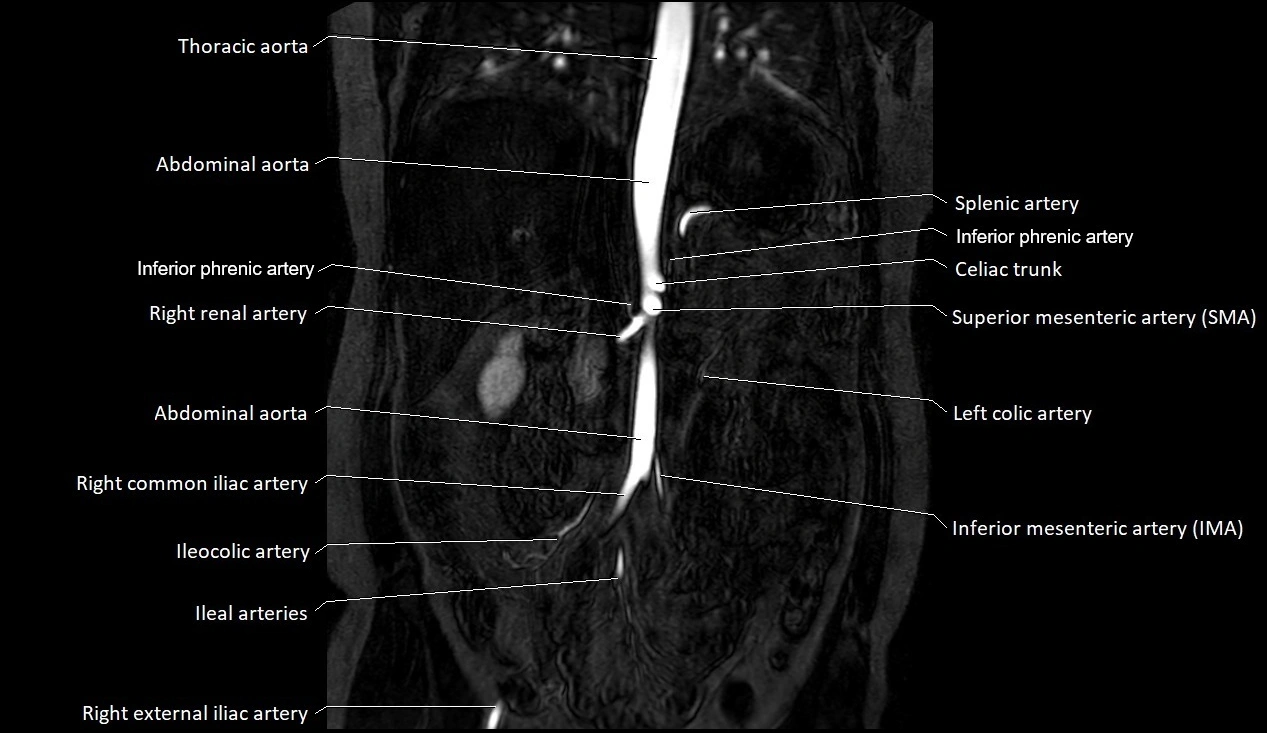

CT images

image